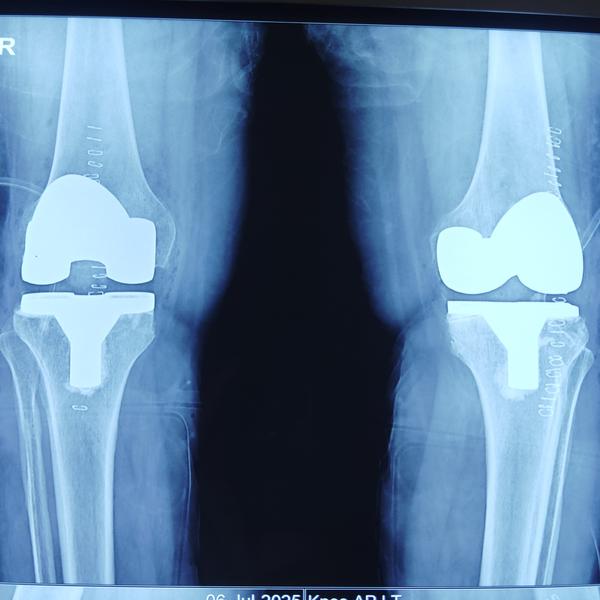

Successful KNEE REPLACEMENT surgery in Greater Noida

Best kee replacement dr in Greater Noida

knee replacement in greater Noida